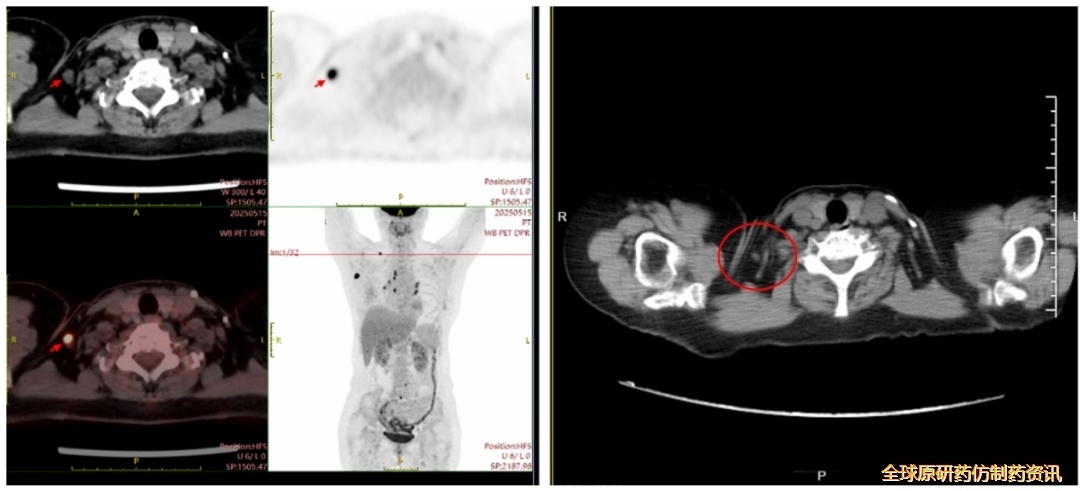

2025-5-15行PET-CT:

右乳术后复查:右侧胸壁术后改变;右侧腋窝结节(1.6*1.5cm),考虑转移或复发;右侧锁骨区散在淋巴结转移;b.右肺上叶术后改变;双肺多发小结节,FDG代谢未见增高,建议随诊;c.L4椎体及L5棘突FDG代谢增高,转移待排,建议结合增强MR检查或密切随诊。

图2 .患者疗效评估

(图左:PET-CT检查,时间2025-5-15;图右:胸部CT检查,时间2025-7-22)